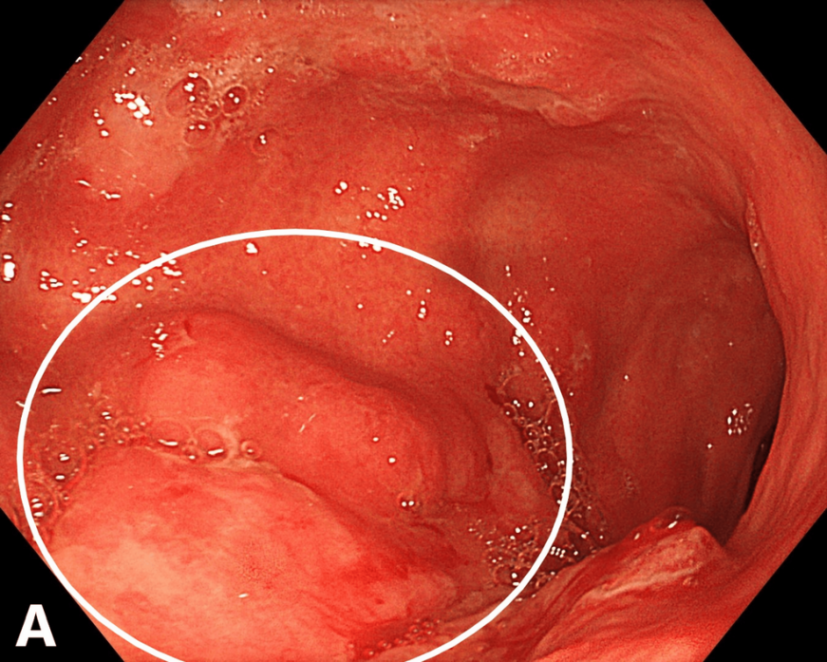

2024年11月29日行上消化道内镜检查,发现贲门闭合不全及远端卡他性食管炎。胃黏膜呈中度水肿及充血。在胃体中下三分之一区域可见一处浸润性溃疡性病变,表面结节样、边缘模糊、可触出血,并进行多次活检(图1)。

图1. 浸润性溃疡性胃部病变,伴黏膜水肿和充血(内镜,2024年11月)